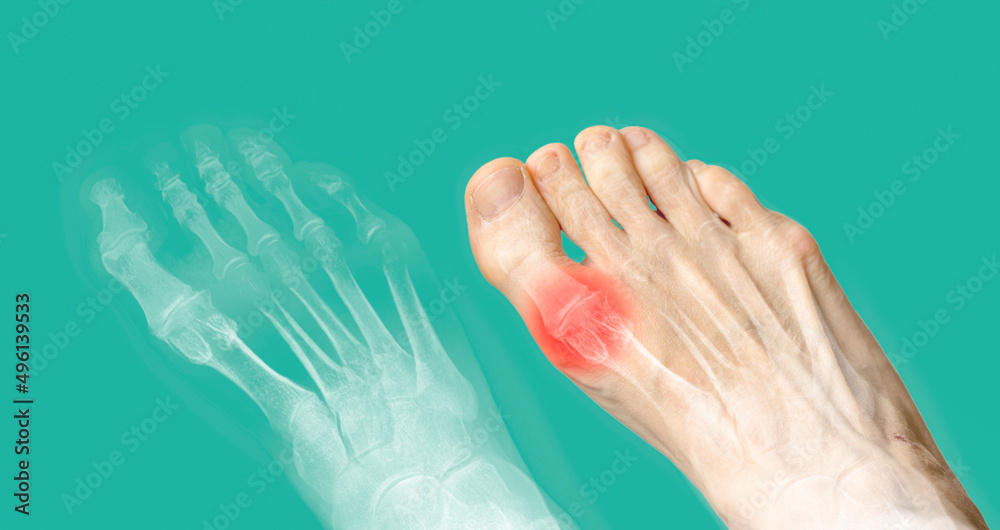

Xray and the same foot with red pain. Rheumatoid arthritis Foot Pain Of Rheumatoid Arthritis foot pain often occurs in the joints or ball of the foot, but rheumatoid arthritis can attack any of the foot's joints. unlike osteoarthritis, which typically affects one specific joint, symptoms of rheumatoid arthritis (ra) usually appear in both feet, affecting the same joints. Read about foot pain treatment options for. conventional joint exams for ra don’t. Foot Pain Of Rheumatoid Arthritis.